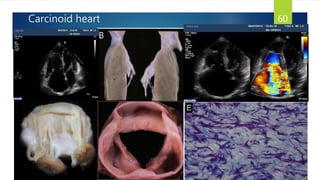

Carcinoid heart 60